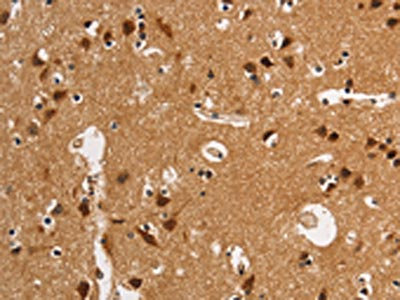

The image on the left is immunohistochemistry of paraffin-embedded Human brain tissue using CSB-PA135409(ANAPC4 Antibody) at dilution 1/50, on the right is treated with synthetic peptide. (Original magnification: ×200)